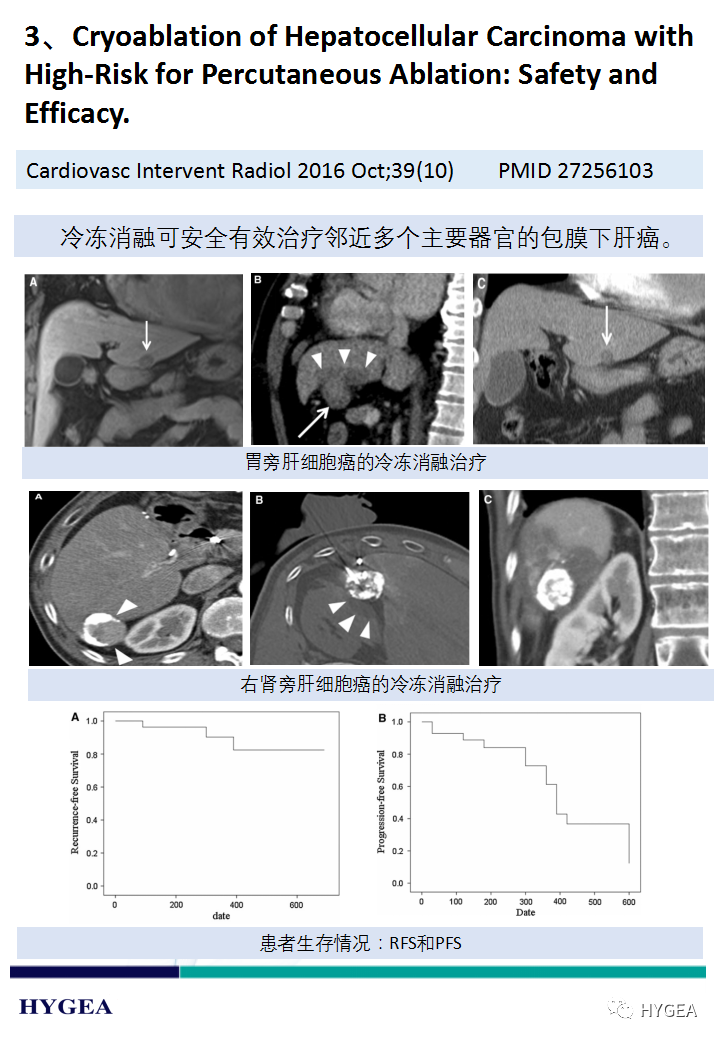

下一頁:【海杰亞科研資訊】第187期——冷凍消融肝癌專題